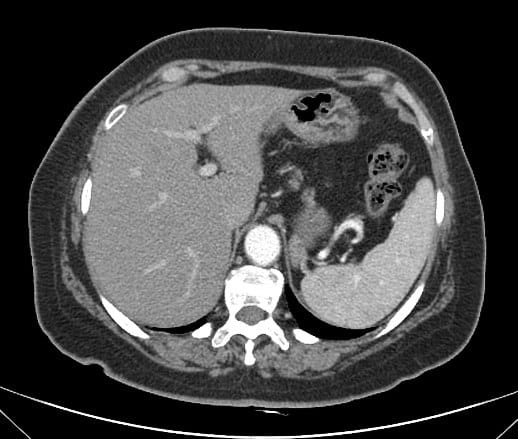

Túi thừa dạ dày

» Thông tin: Nữ giới – 50 tuổi.

» Lâm sàng: Kiểm tra sức khỏe.